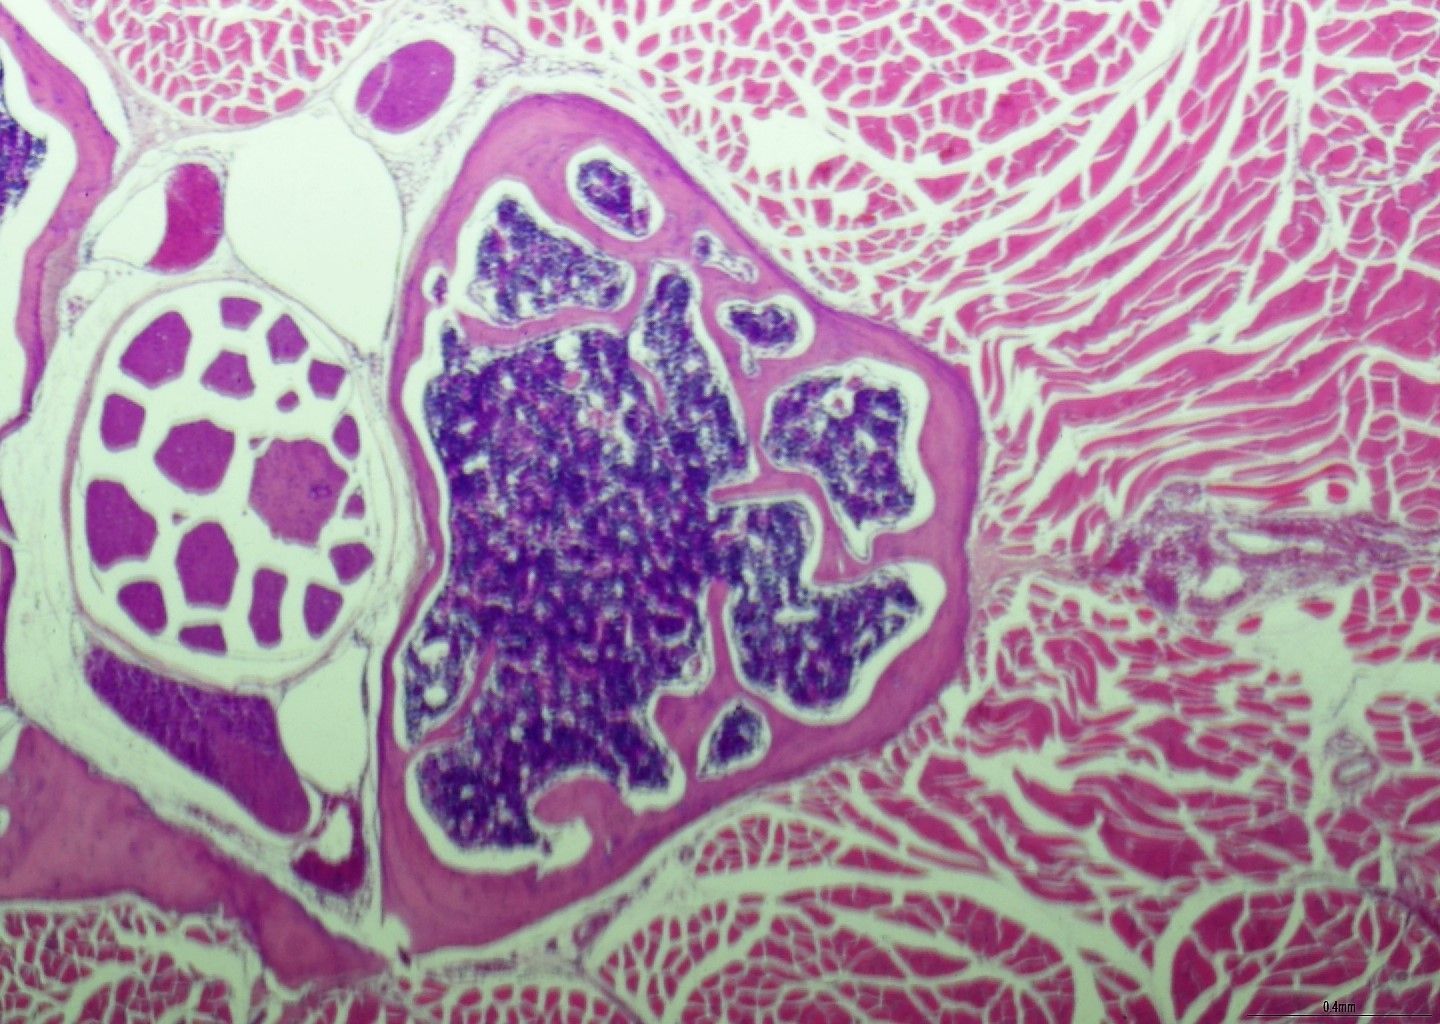

- Επίδειξη συγκεκριμένων στόχων αιμοσφαιρίων κατά τη βιοψία BMT